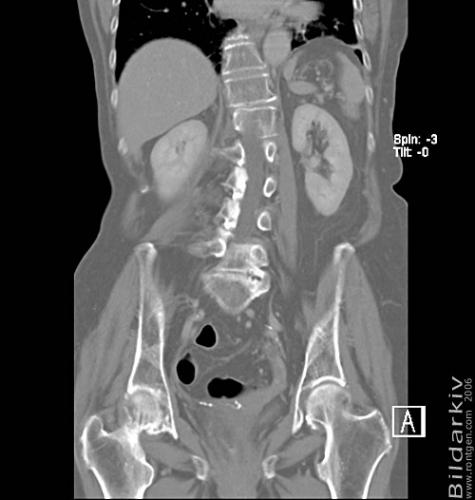

CT colon 35

Datortomografi av tjocktarmen (colon) med infunderad luft i tarmen samt med kontrast i blodbanan. Koronar bildserie.

CT multislice 16